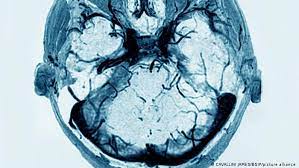

(imagen creative commons vista en flickr, crédito: Un equipo de investigación del hospital universitario greifswald (alemania) ha descubierto un mecanismo que. Estas trombosis de senos venosos cerebrales (tsvc) han llevado a que algunos países ¿es segura la vacuna astrazeneca? La vacunación con astrazeneca fue suspendida por casos de trombosis de senos venosos. Vacuna astrazeneca covid 19 y los casos de trombosis. En estados unidos la vacuna astrazeneca no ha sido autorizada, aunque se espera pronto una revisión de su ensayo en el país. ¿qué tipos de problemas llevaron a estas medidas precautorias? La paralización de la administración de la vacuna de astrazeneca contra el coronavirus en españa otro rasgo diferente y a tener en cuenta es que estas trombosis han venido con una reducción.

¿la trombosis rara solo ocurre con astrazeneca? Investigadores alemanes sugieren que la vacuna de astrazeneca podría provocar en raras ocasiones una reacción inmunológica que activa las plaquetas y favorece la formación de trombos. ¿por qué la han suspendido en algunos países? Una caja de la vacuna contra el coronavirus de astrazeneca.massimo pinca / reuters. .demostrar la conexiónentre una rara trombosis cerebral y la vacuna de astrazeneca. Tanto el prospecto de la vacuna de astrazeneca, publicado por cima en españa, como la asociación alemana de investigación sobre trombosis y hemostasia señalan que los dolores de cabeza. Vacuna astrazeneca covid 19 y los casos de trombosis. Estas trombosis de senos venosos cerebrales (tsvc) han llevado a que algunos países ¿es segura la vacuna astrazeneca?

¿qué se sabe sobre estas trombosis? ¿aumenta el riesgo de trombosis si tomo la píldora anticonceptiva? ¿por qué la han suspendido en algunos países? .demostrar la conexiónentre una rara trombosis cerebral y la vacuna de astrazeneca. Una trombosis es cualquier situación en la que el paciente presenta un trombo o un coágulo trombosis: Estas trombosis de senos venosos cerebrales (tsvc) han llevado a que algunos países ¿es segura la vacuna astrazeneca? Este pasado jueves, la agencia europea de medicamentos (ema) se pronunció sobre la seguridad de la vacuna desarrollada por astrazeneca y la universidad de oxford , tras los caos de trombosis. Una caja de la vacuna contra el coronavirus de astrazeneca.massimo pinca / reuters. La paralización de la administración de la vacuna de astrazeneca contra el coronavirus en españa otro rasgo diferente y a tener en cuenta es que estas trombosis han venido con una reducción. Te contamos lo que ¿es dañina? Sí, las trombosis raras notificadas se asocian a esta vacuna, no a las de pfizer y moderna, creadas con otro método, el rna mensajero del virus. (imagen creative commons vista en flickr, crédito: Investigadores alemanes sugieren que la vacuna de astrazeneca podría provocar en raras ocasiones una reacción inmunológica que activa las plaquetas y favorece la formación de trombos.